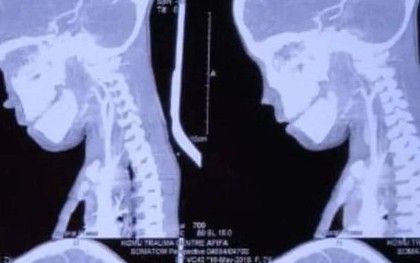

Phẫu thuật cho bé trai 7 tuổi, bác sĩ sốc nặng khi lấy ra "thứ đáng sợ"

Sự việc xảy ra khi bé trai vô tình ngã xuống đất khi đang chơi và trúng một chiếc đinh sắt, đâm xuyên qua cổ và chạm đến vùng não cực kỳ nhạy cảm.